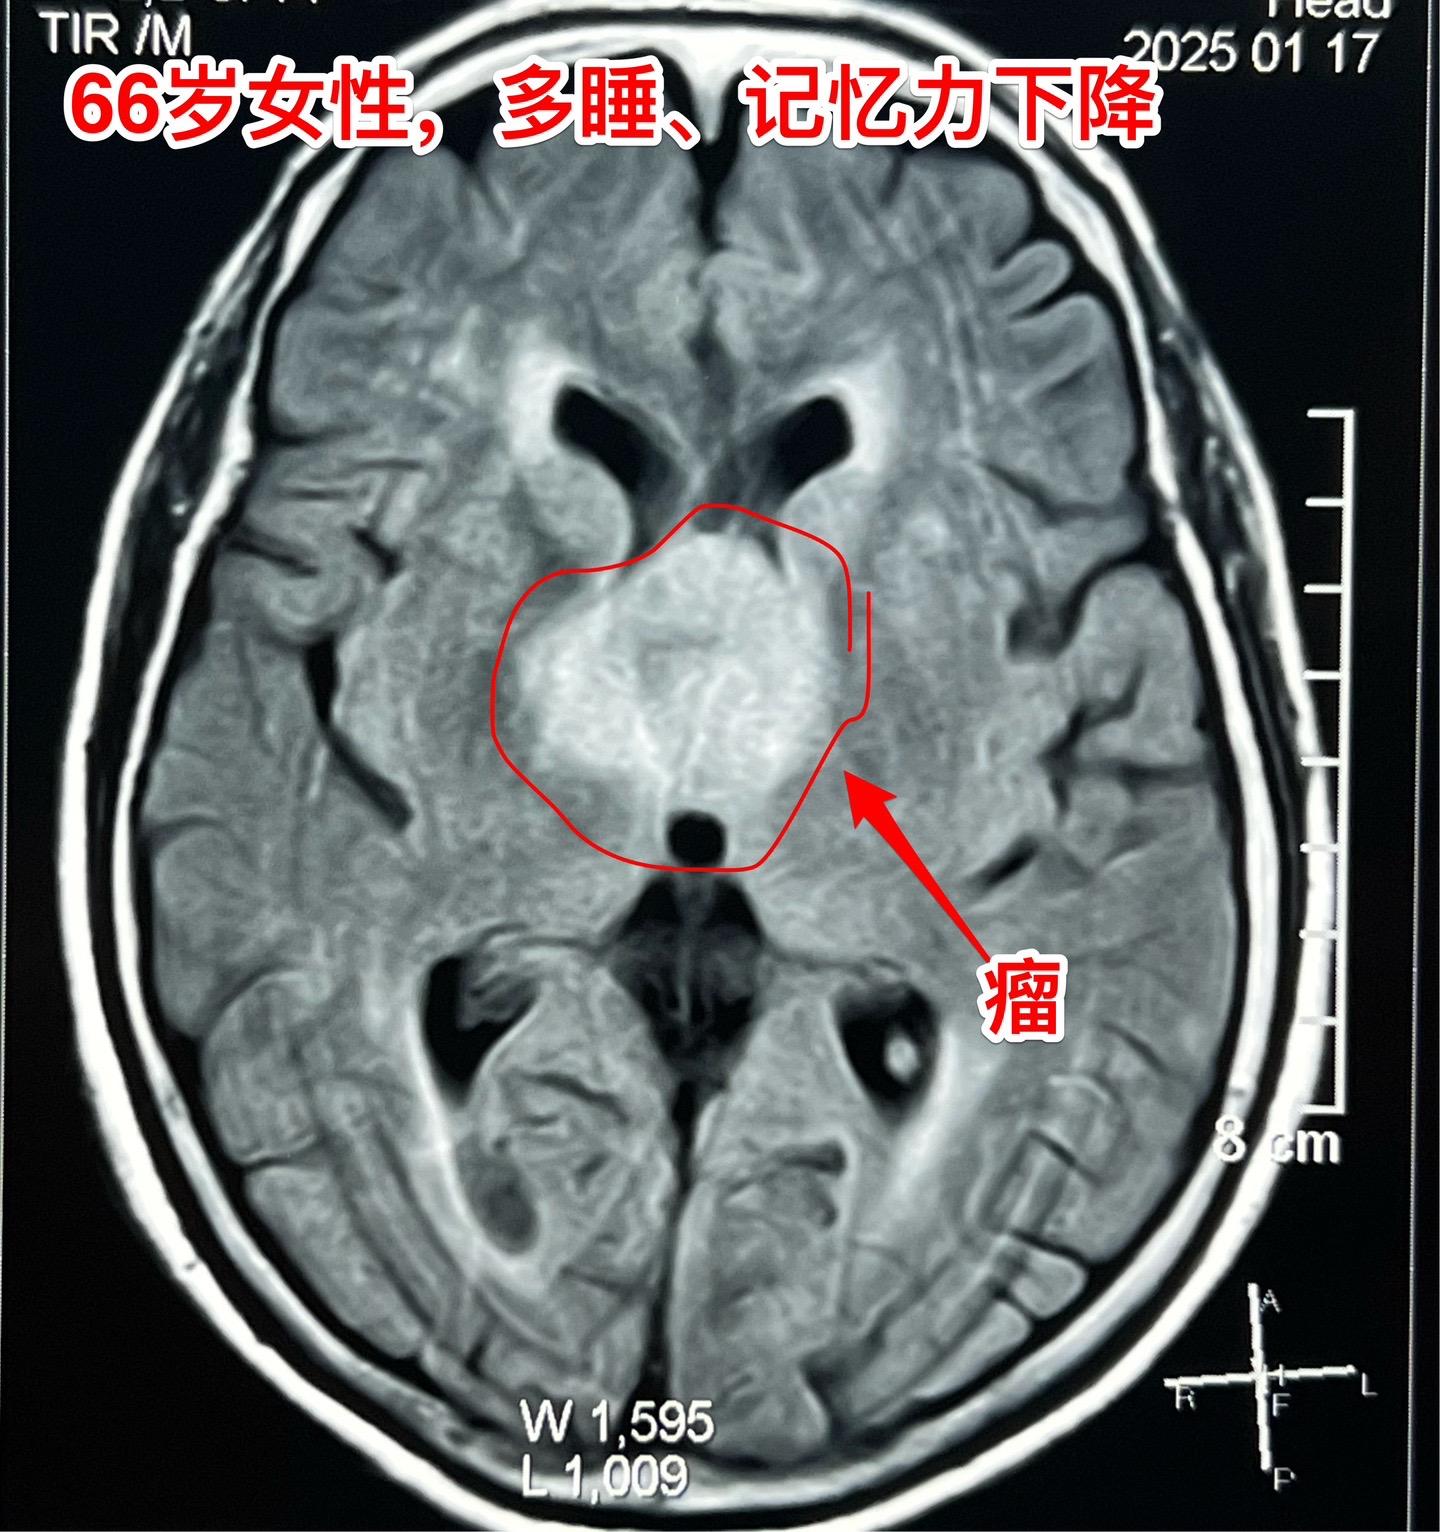

是颅咽管瘤吗?鞍区肿瘤的定性诊断是很难的。66岁女性,泰州人。因为多睡、记忆力下降在外院检查脑部发现脑部肿瘤。病人的多睡症状越来越严重。肿瘤位于鞍上区域,而且伴有脑积水。外院怀疑是颅咽管瘤?或者是别的肿瘤? 病人曾经在上海就医过,因担心手术风险,通过三博脑科医院院长找我咨询,随后决定到我院作手术。 1月24日作了开颅手术(这是我科春节前的最后一个择期手术),手术中发现肿瘤的性状不符合乳头型颅咽管瘤,分两次取标本送快速冰冻病理检查,报告考虑是胶质瘤。 下丘脑胶质